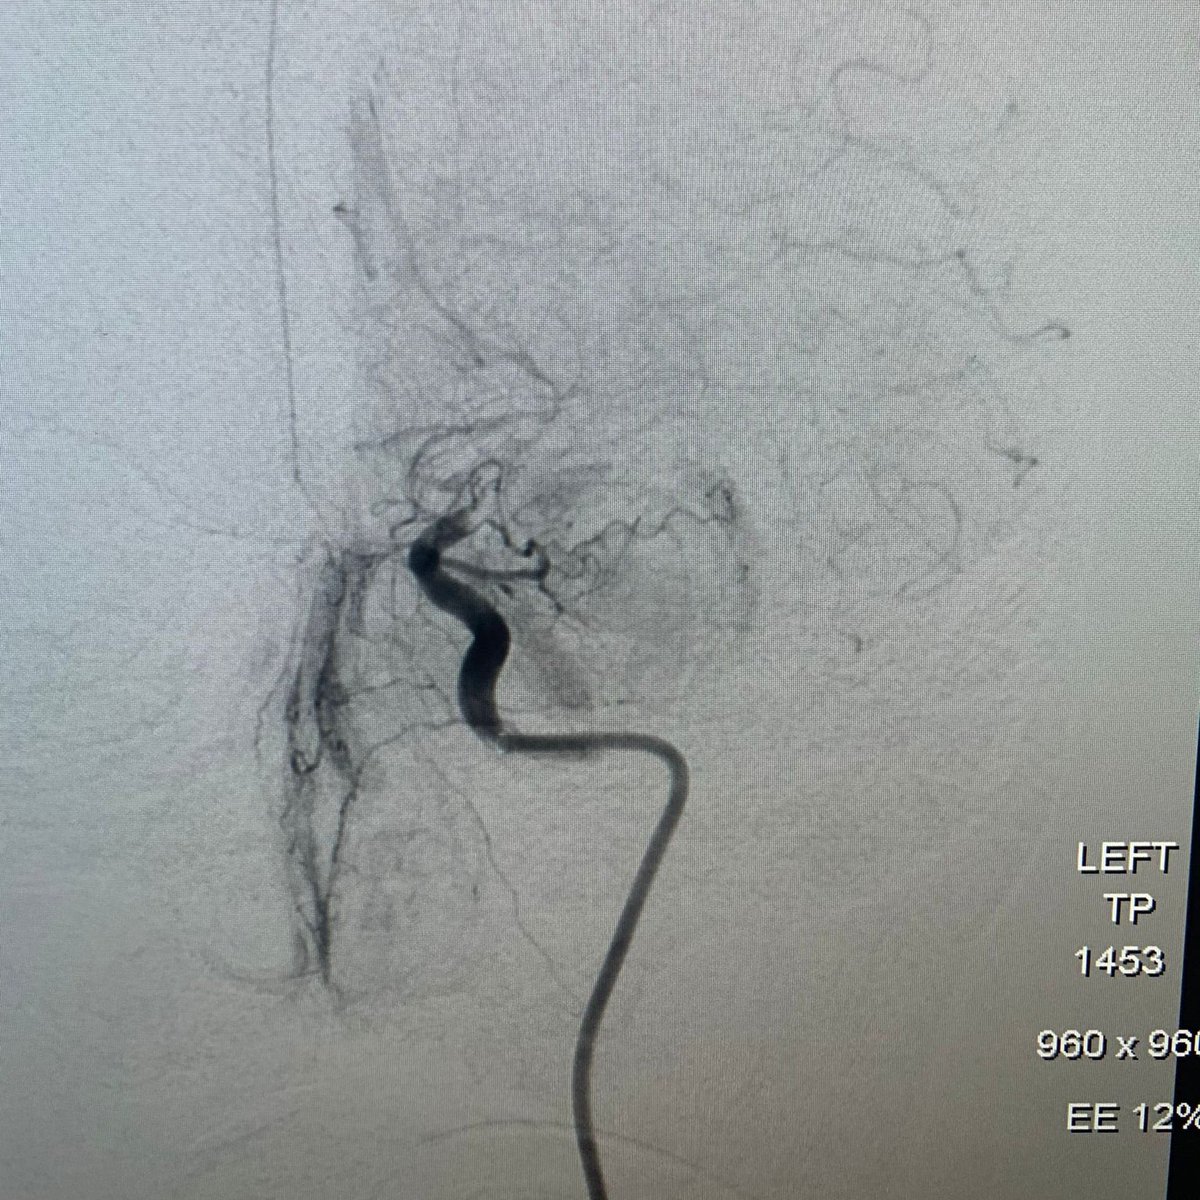

#Tigertriever's Debut in the Northeast! Dr. Sid Roychowdhury Robert Wood Johnson University Hospital in New Brunswick, NJ treated a 61 y/o patient with a history of Afib. Left MCA occlusion treated with #Tigertriever (1 pass, TICI 3) and ACE68. #Tigertriever inflated 3 times to integrate and capture the clot.